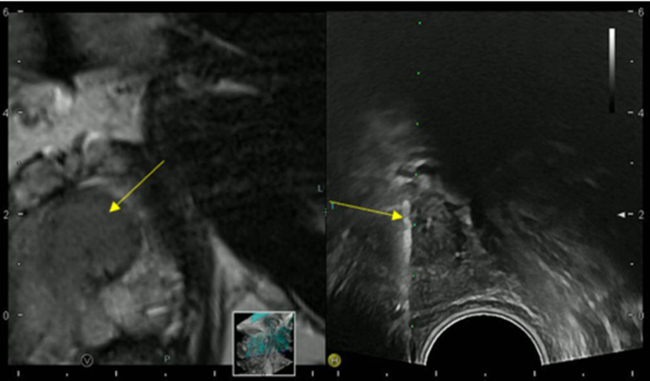

The simultaneous application of structural and functional imaging techniques is described as multiparametric (MP) (Fig. 9). Studies have shown that the MP approach results in greater diagnostic accuracy (Fig. 10).

The use of fusion imaging in uroradiology improves ultrasound lesion-detection rates, shows more reliable size controls at different time points, is an alternative to in-bore biopsies (Fig. 11) and can be used for focal therapy.